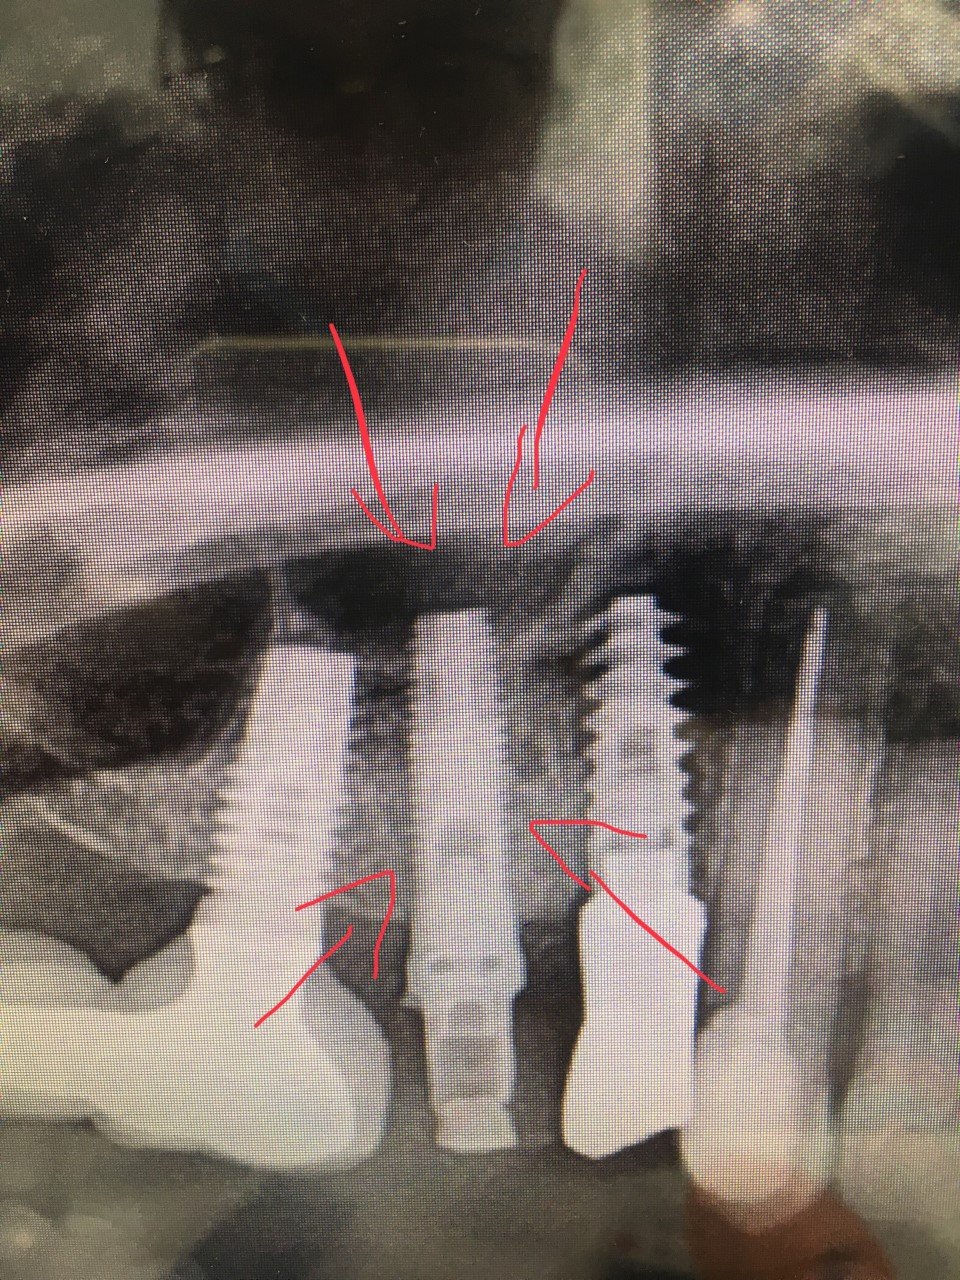

La paciente tiene la corona del 46 en infraoclusión, y necesito modificar la corona de la misma para llevarla a una oclusión correcta. No he levantado la corona, por si [...]

Se ha fracturado el tornillo pasante